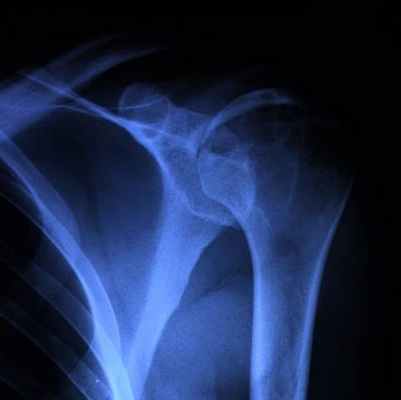

Хондробластома — редкая опухоль, составляет 1–1,8% первичных опухолей кости (10% всех опухолей скелета). Возникает преимущественно в детском и юношеском возрасте. Излюбленная локализация — длинные трубчатые кости. Поражает эпифизы и метафизы (проксимальный и дистальный отделы бедренной кости, проксимальные отделы большеберцовой и плечевой костей), реже — кости таза и лопатки • Клиническая картина. Превалирует боль, отмечается небольшая припухлость, иногда ограничение движений в суставе и гипотрофия мышц • Диагностика. Рентгенологически определяют неоднородный очаг деструкции округлой или овальной формы. Дифференциальную диагностику хондробластомы проводят с солитарной энхондромой и литической формой остеобластокластомы • Лечение хондробластомы хирургическое (кюретаж), однако, учитывая возможность малигнизации, рекомендуют резекцию кости.

(Слева) Рисунок: срез проксимального отдела плечевой кости с типичной хондросбластомой. Показан эпифизарный, эксцентрично расположенный очаг с четкими границами. Патологическое образование имеет склеротический край и содержит кальцинаты.

(Справа) Рентгенография: классическая хондробластома у пациента с почти зрелым скелетом. Литический очаг развивается в эпифизе и распространяется на метафиз. Очаг не содержит кальцинированный матрикс, имеет четкие границы и умеренно склерозированный край. (Слева) МРТ, корональная проекция, режим Т1: однородный, эксцентрично расположенный эпифизарный очаг, типичный для хондробластомы. В зоне метафиза визуализируется массивная периостальная реакция типичный признак в 50% случаев.

(Справа) КТ, аксиальная проекция, без контрастного усиления: весьма эксцентрично расположенная хондробластома эпифиза плечевой кости. Она содержит небольшое вкрапление кальцинированного матрикса и немного вспучивает кортикальный слой. Этому пациенту с жалобами на боль и пощелкивание при ротации плеча, в первую очередь, вместо лучевого исследования, было необоснованно выполнено артроскопическое вмешательство.